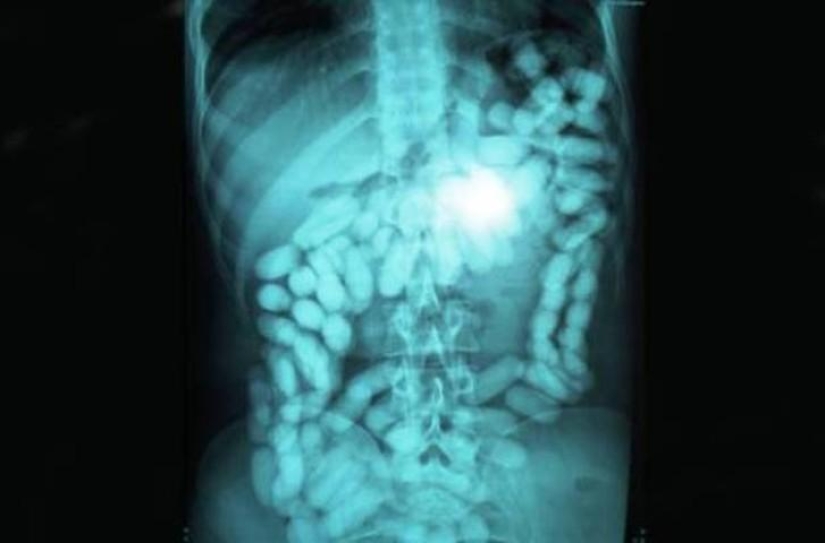

23. Methamphetamines.